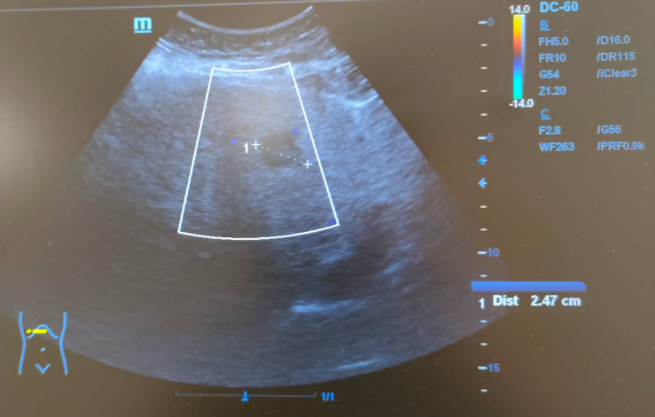

Hallazgos ecográficos

Hígado de tamaño normal, contornos ligeramente nodulares, alteración de la ecoestructura compatible con hepatopatía crónica. Nódulo hipoecoico de contornos irregulares en lóbulo hepático izquierdo de 16x24mm sin captación Doppler.